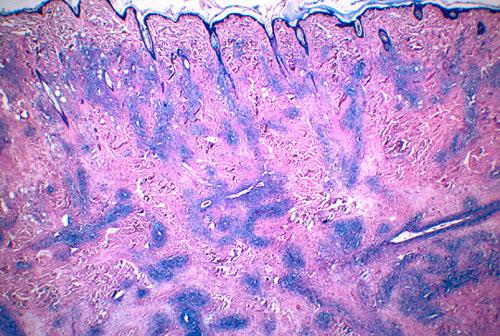

Enfin, un examen histopathologique des lésions a été demandé sur les derniers prélèvements. Les images observées étaient compatibles, dans la mesure ou le caractère stérile était démontré, avec un histiocytose réactionnelle (photo 4 et 5).

histiocytose-cutanee4

Photo 4 : lésions nodulaires à diffuses de tropisme vasculaire

présentes à tous les niveaux du derme (HE, x 40)